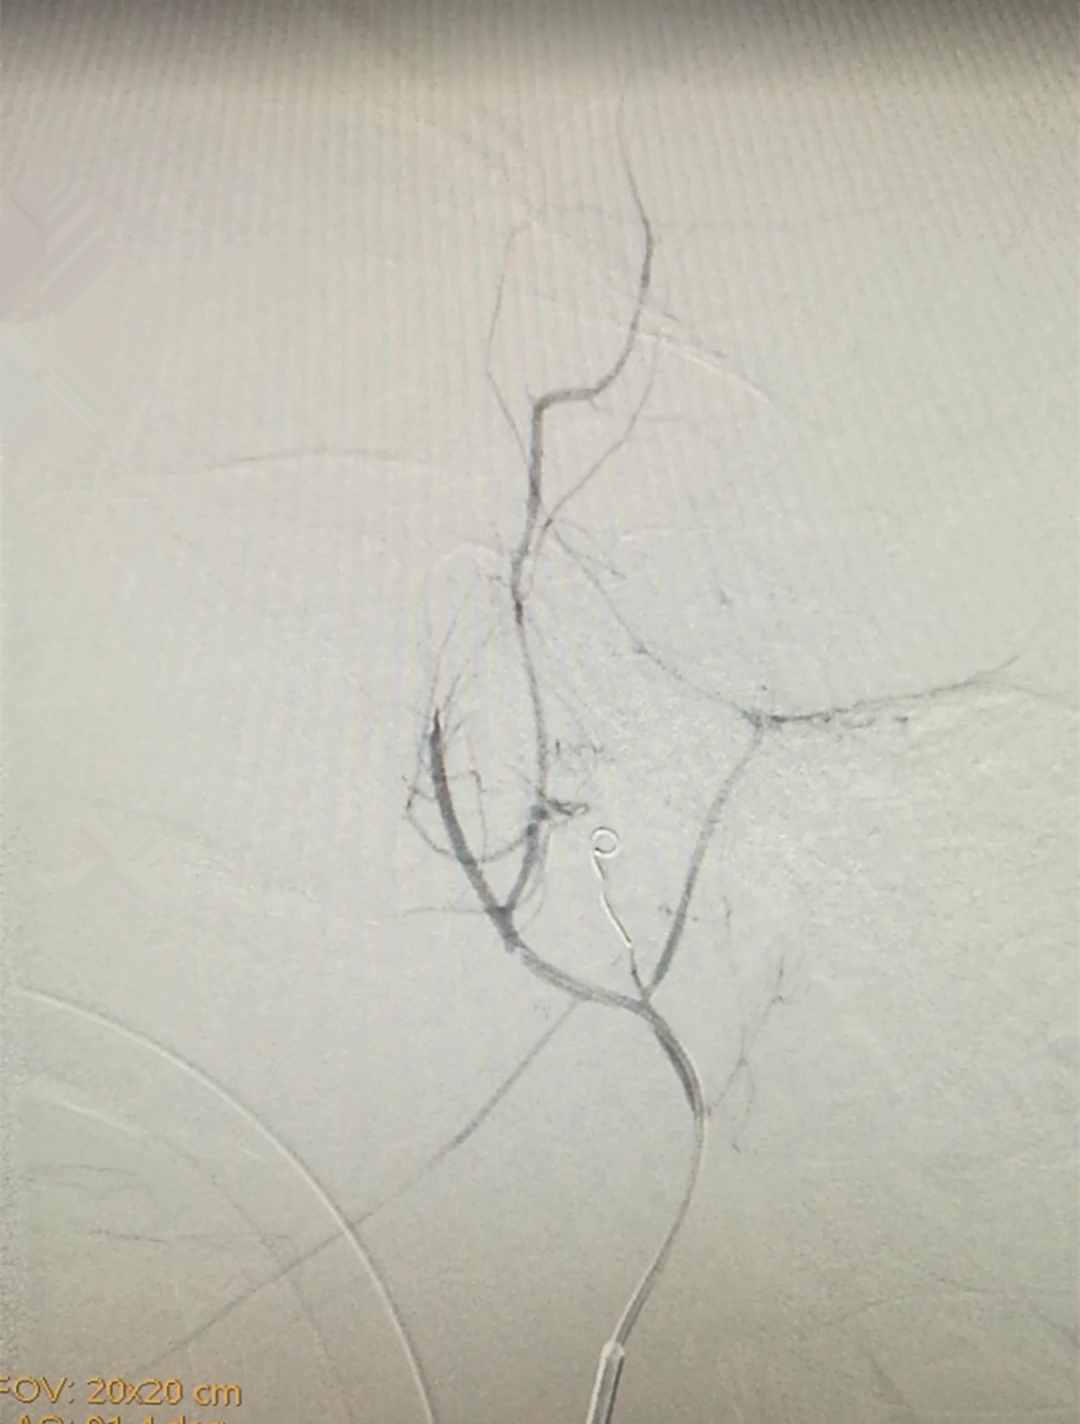

栓塞前

栓塞后

挽救生命,刻不容缓。以副院长向华、介入血管外三科主任颜鹏为首的医疗团队在手术中造影后发现患者颈外动脉颅内、颅底分支血管破裂。介入血管外三科医疗团队从患者右侧大腿部的股动脉米粒大的穿刺口送入一根1米多长的导管,顺着血管延伸至颅内出血部位,再将细如发丝的弹簧圈填塞到血管破裂处,进行栓塞。再次造影后显示出血部位止血了,躺在手术台上的患者口、鼻腔流血立马停止,效果立杆见影。通过团队配合,经过一个多小时,手术顺利完成。在医护人员的精心治疗下,目前患者成功脱机拔管苏醒顺利出院了。